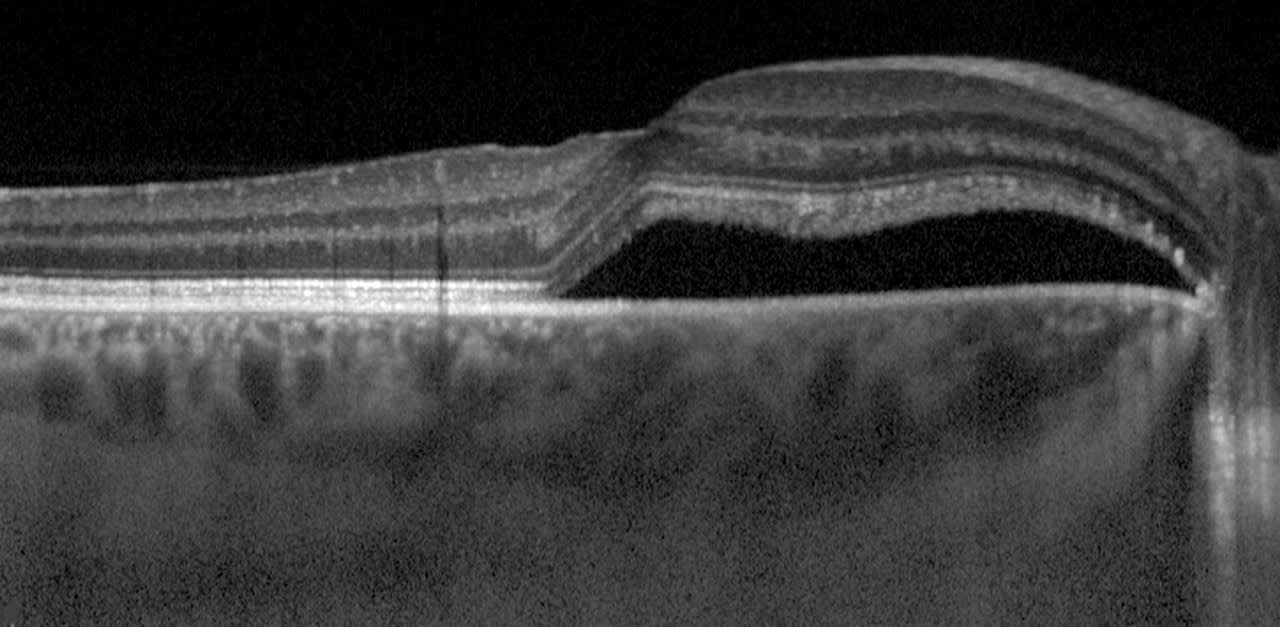

In some cases, a “simple” OCT scan can confirm or better illustrate a diagnosis. One of the more common uses of this is in the case of determining a retinal detachment vs retinoschisis. When done properly, OCT can provide definitive data to differentiate between an actual retinal detachment, a separation of all retinal layers or retinoschisis, which is a separation within the normal retinal layers (Figures 6 and 7)